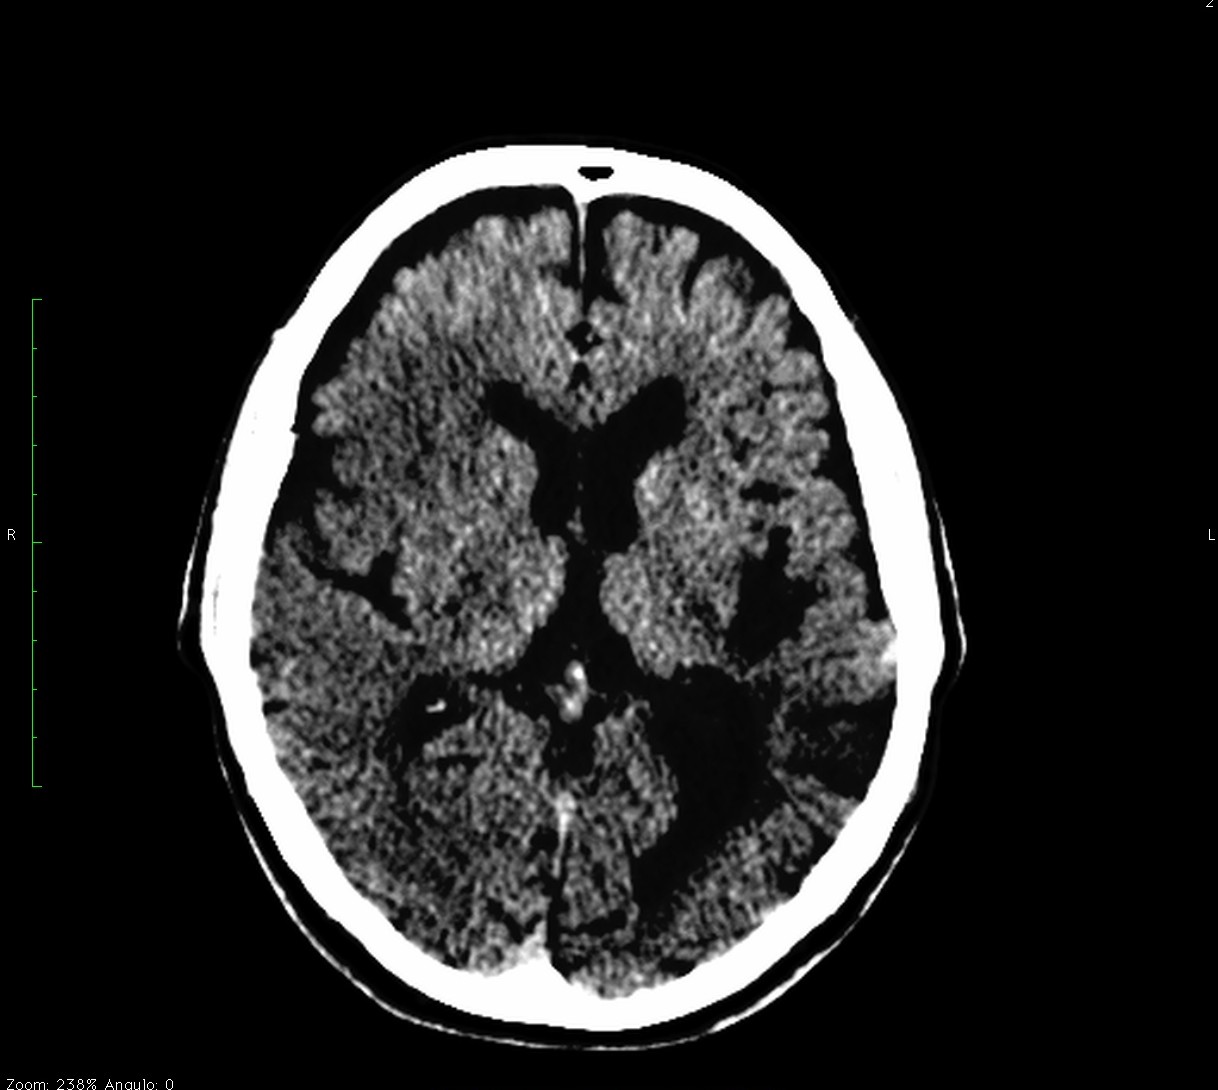

Se investiga un poco más y se descubre que el paciente había acudido diez días antes, también con cierta clínica de debilidad en hemicuerpo izquierdo, y se le realizó un TAC de cráneo. Observemos por tanto el estudio previo:

Pues bien, ante los hallazgos descritos, se clarifica que estamos ante un paciente el cual no tiene una masa y que ha sufrido una lesión isquémica hace diez días. Ahora, sobre dicha lesión, tenemos una imagen con un aumento de densidad que sugiere sangrado por una parte y otra hipodensidad en la perifería que correspondería a un edema. Por tanto, descartamos un sangrado intraparenquimatoso de novo. El paciente tiene más de 65 años, no es hipertenso, la imagen del sangrado no es de alta densidad, lo que se opone a una fase aguda o hiperaguda, y tenemos el TC de cráneo previo donde ya se advertía un proceso de tipo isquémico. Por tanto, nos quedan dos opciones, o estamos ante un resangrado de un ACV o estamos ante una Perfusión de lujo.

Vistos los tiempos en los que puede acontecer cada proceso y la atenuación radiológica que se obtiene con la TAC, puede ser dificil distinguir un ACV con transformación hemorrágica, sobre todo si está más evolucionado, de una perfusión de lujo. Necesitaríamos establecer un cronograma radiológico, donde observásemos la evolución de la sangre. En nuestro caso, dadas la evolución y la correlación con la imagen, nos orientaríamos más hacia una perfusión de lujo.